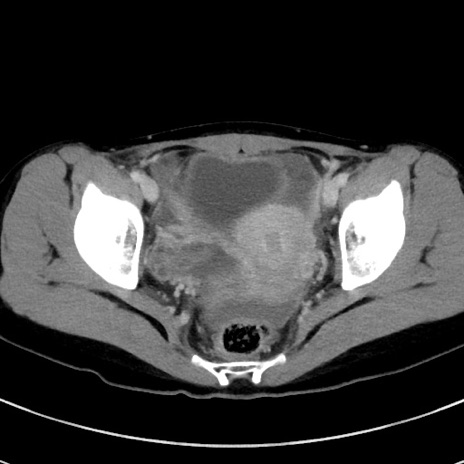

症例17(横断像)

【症例】20歳代女性

【主訴】嘔吐、下腹部痛

【現病歴】昨日夕食後に嘔吐し下腹部痛が出現。本日になっても嘔吐持続し改善しないため来院。

【身体所見】意識清明、BT 37.2℃、BP 108/67mmHg、腹部:平坦、やや硬、下腹部正中から右にかけて圧痛あり、反跳痛軽度あり、tapping pain(+)。

【データ】WBC 13600、CRP 14.94